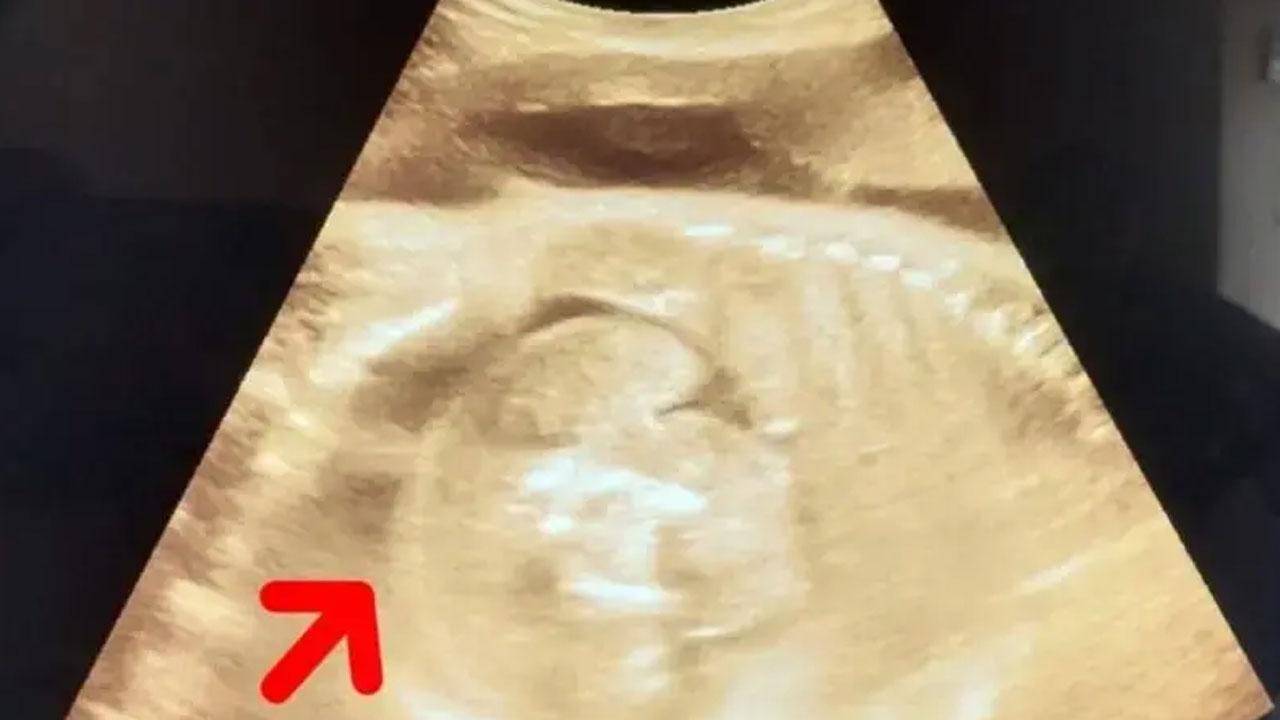

নারীর গর্ভে থাকা শিশুর গর্ভে মিলল আরও একটি ভ্রূণ প্রকাশিত: ১১:৫৬ পূর্বাহ্ণ, ফেব্রুয়ারি ১, ২০২৫ ভারতের মহারাষ্ট্রে এক নারীর গর্ভে থাকা শিশুর শরীরে আরও একটি ভ্রূণের সন্ধান পাওয়া গেছে। সম্প্রতি ওই নারী সোনোগ্রাফি করানোর জন্য হাসপাতালে যান। তখন চিকিৎসকরা এ বিষয়টি লক্ষ্য করেন। তবে চিকিৎসকরা জানিয়েছেন, ওই নারীর শারীরিক অবস্থা স্থিতিশীল রয়েছে। জানা যায়, ৩২ বছরের ওই নারী তার গর্ভাবস্থার অষ্টম মাসে সোনোগ্রাফি করাতে গত বুধবার হাসপাতালে যান। তখন পরীক্ষা করে জানা যায়, ওই নারীর গর্ভে যেমন একটি শিশু রয়েছে, তেমনই ওই শিশুর গর্ভেও একটি ভ্রূণ রয়েছে। বিষয়টি সম্পর্কে নিশ্চিত হতে চিকিৎসক এবং বিশেষজ্ঞদের একটি টিম আরও একবার সোনোগ্রাফি করেন। তখনও গর্ভে থাকা শিশুটির গর্ভে একটি ভ্রূণ স্পষ্টভাবে দেখা যাচ্ছিল। হাসপাতালের এক শল্যচিকিৎসক (সিভিল সার্জন) বলেছেন, সোনোগ্রাফি পরীক্ষার পর দেখা যায়, ওই নারীর গর্ভে একটি শিশু রয়েছে এবং শিশুটির গর্ভে আরও এক শিশু রয়েছে। তবে একে ঠিক শিশু বলা যাবে না, কারণ এটি ফিটাল মাস। এক অর্থে বলতে গেলে, এটি একটি মাংসের পিণ্ড। ‘এটি জীবিত শিশু নয়, কারণ তার হৃদস্পন্দন নেই। দেখতে শিশুর মতো মনে হয় বলেই একে বেবি বলা হয়।’ বিষয়টিকে আরও বিশদে ব্যাখ্যা করে তিনি বলেন, ওই মাংসপিণ্ড আকারে বৃদ্ধি পাচ্ছে, কারণ সেখানে রক্ত সরবরাহ অব্যাহত রয়েছে। ডাক্তারি ভাষায় একে ফিটাস ইন ফেটু (ভ্রূণের অভ্যন্তরে ভ্রূণ) বলা হয়। ফিটাস ইন ফেটু কী? ফিটাস ইন ফেটু এমন একটি বিরল বিকাশজনিত অস্বাভাবিকতা যেখানে গর্ভজাত ভ্রূণের গর্ভে আরও একটি ভ্রূণ তৈরি হয়। গবেষণা বলছে, ‘ফিটাস ইন ফেটু’ একটি বিরল এবং ব্যতিক্রমী ঘটনা। এই সমস্ত ক্ষেত্রে নারীর গর্ভে থাকা শিশুর গর্ভে আরও একটি ভ্রূণ তৈরি হয়, যা অনুন্নত। সাধারণত, ওই ভ্রূণ গর্ভে থাকা শিশুর গর্ভে একটি পিণ্ডের আকারে দেখা যায়। মায়ের গর্ভে থাকা অবস্থায় শিশুর বৃদ্ধির সঙ্গে সঙ্গে ওই শিশুর পেটে থাকা পিণ্ডও আকারে বৃদ্ধি পেতে থাকে। চিকিৎসা ‘ফিটাস ইন ফেটু’র ক্ষেত্রে যে শিশুর গর্ভে অন্য ভ্রূণ বা সঠিকভাবে বলতে গেলে মাংসপিণ্ড রয়েছে, তার সার্জারি বা অস্ত্রোপচারের প্রয়োজন হয়। ভ্রূণ অপসারণ করার পর সাধারণত শিশু সুস্থ হয়ে ওঠে। উল্লেখ্য, ভ্রূণের মধ্যে ভ্রূণ-এটি অত্যন্ত বিরল ঘটনা। গবেষণা অনুযায়ী, গোটা বিশ্বে এমন ঘটনা পাঁচ লাখে একটি। SHARES আন্তর্জাতিক বিষয়: নারীভ্রূণেরসম্প্রতি